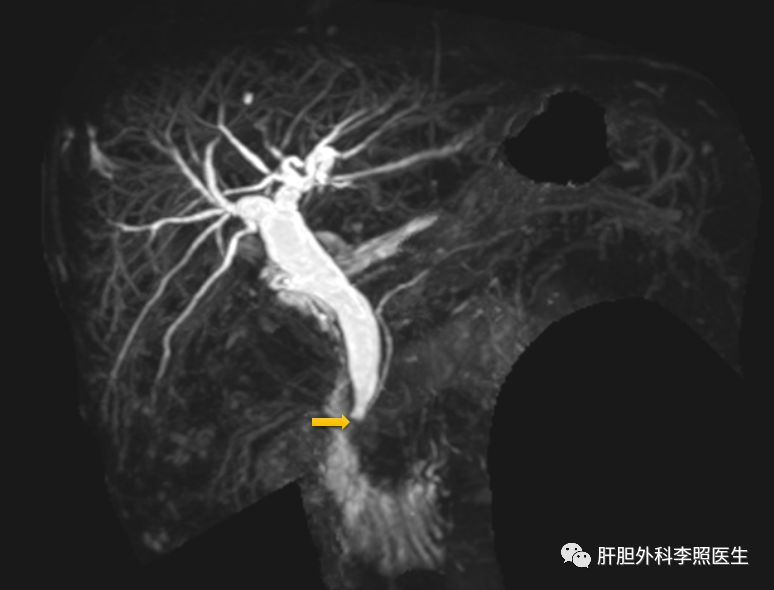

SOD典型的核磁图像,可以看到胆总管末端呈鸟嘴样表现(黄色箭头指向)

● B超、CT、MRCP或ERCP显示胆总管直径>12 mm(毫米),胆总管下端呈鸟嘴状狭窄。